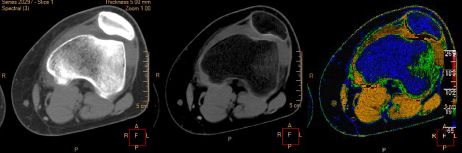

●さらに高まる診断確度Calcium Suppression

骨髄イメージングを描出するカルシウム抑制画像が新たにスペクトラルリザルトに追加された。従来のCTでは骨の高いコントラストにより表現が難しかった骨挫傷の診断において,カルシウム成分を抑制した画像を用いることで骨髄浮腫の状態を可視化し,MRI等の追加の検査削減や確定診断までの時間短縮を図る。